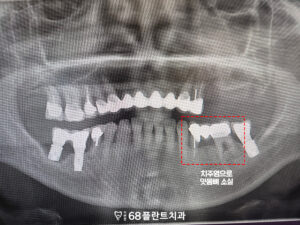

확인해 보니,

전체적으로 치료한 부위가 많았으나

관리가 제대로 되지 않아

치주염이 발생하였고,

그로 인해 잇몸뼈가 녹아

뼈가 소실되었습니다.

또한 오른쪽 아래 임플란트와

치아도 염증으로 인해 뼈가 녹아

제 기능을 못하고 있었습니다.

마지막으로 위쪽의 롱 브릿지도

힘을 받고 있는 지대치쪽으로 잇몸뼈가 소실되어,

브릿지의 안정성이

크게 떨어지고 있었습니다.